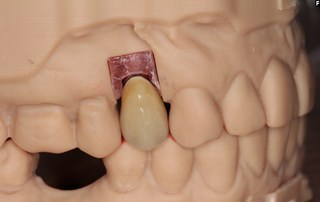

Våra tandtekniker på "Fenix Dentalteknik" i Örebro framställer en krona.

Kronan kan antingen monteras som på bilden med en centrumskruv alternativt cementeras fast på en distans.

Kronan klar för montering i munnen